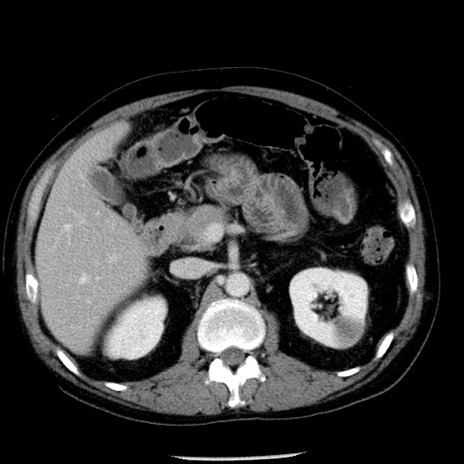

症例29(横断像)

【症例】40歳代男性

【現病歴】2日前から胃痛あり。徐々に周期的な激痛に変化した。本日になっても激痛があるため受診。

【身体所見】意識清明、BT 38-39℃台あり、腹部:膨満、やや硬、右下腹部に圧痛あり。

【データ】WBC 8500、CRP 23.26